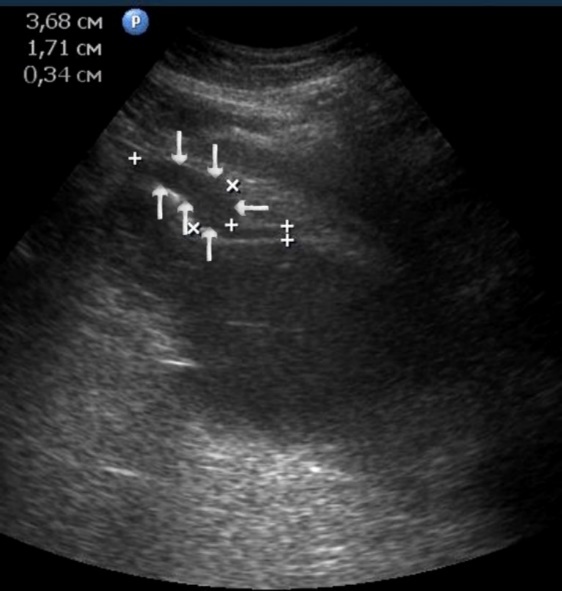

The polypoid type of gastric cancer was observed in 3 (4,9±2,8%) cases, the ulcerative type – in 18 (29,5±5,8%), the infiltrative ulcerative type – in 27 (44,3±6,4%) and the diffuse infiltrative type – in 13 (21,3%±5,2%) cases respectively (Table 2). On the echogram, the tumor was

Visualized as a polypoid formation on a wide base above the gastric mucosa of a non-uniform structure, an irregular surface (Figure 5, Figure 6, Figure 7).

Figure 5.The polypoid type of gastric carcinomas for T3 stage. On the posterior wall of the antrum, a polypoid formation with a fuzzy contour is visualized, the image of the mucous and serous membranes (arrows) is discontinuous.

Figure 6.The gastric carcinoma for T3 stage. The tumor is visualized as a polypoid formation on a wide base above the gastric mucosa of a non-uniform structure, an irregular surface (arrows).

Figure 10.The gastric carcinoma of diffuse infiltrative form. An area with a local thickening up to 1,7 cm, a length of 3,68 cm, is visualized on the anterior wall of the antrum (arrows). The thickening of the normal stomach wall is 0,34 cm.